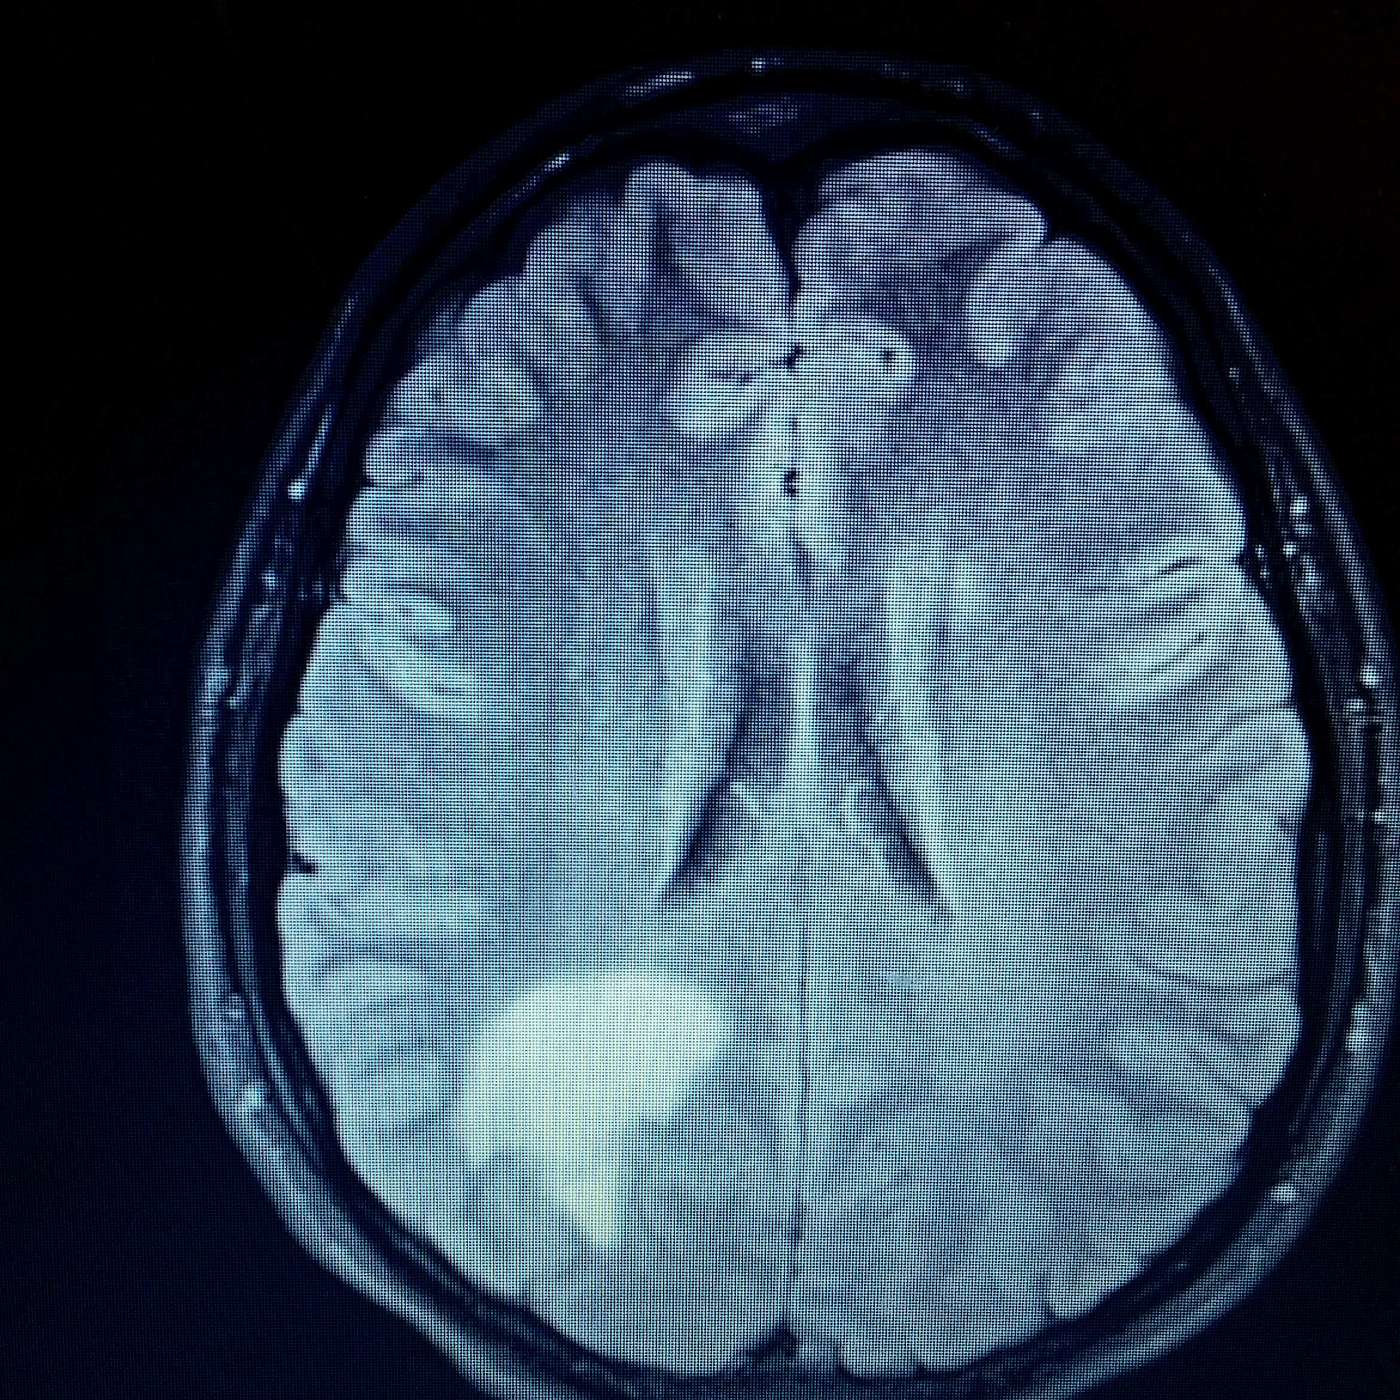

Welcome Back to the Iron Works Podcast! Imagine you are in your mid 20's, at the top of your physical fitness, a leader in a highly specialized unit of the US Army  and under the assumption you are virtually unstoppable.... until one morning you wake up to a diagnosis that knocks you off your feet and takes your life in the complete opposite direction. Our guest today is former US Army Ranger Nathan McCrary, who until that fateful day thought that he would have a long career in the military until he was hit with acute onset Multiple Sclerosis. Join us today as we talk through his journey and the trials along the way, some of which included a Traumatic Brain Injury (TBI) and PTSD diagnosis.